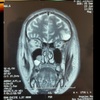

Estudio de imagen que se solicita para sinusitis

Tomografía de nariz y senos paranasales

*Gold standard

En que px se indica la TC para sinusitis

Oncológicos, inmunosuprimidos y sinusitis crónica